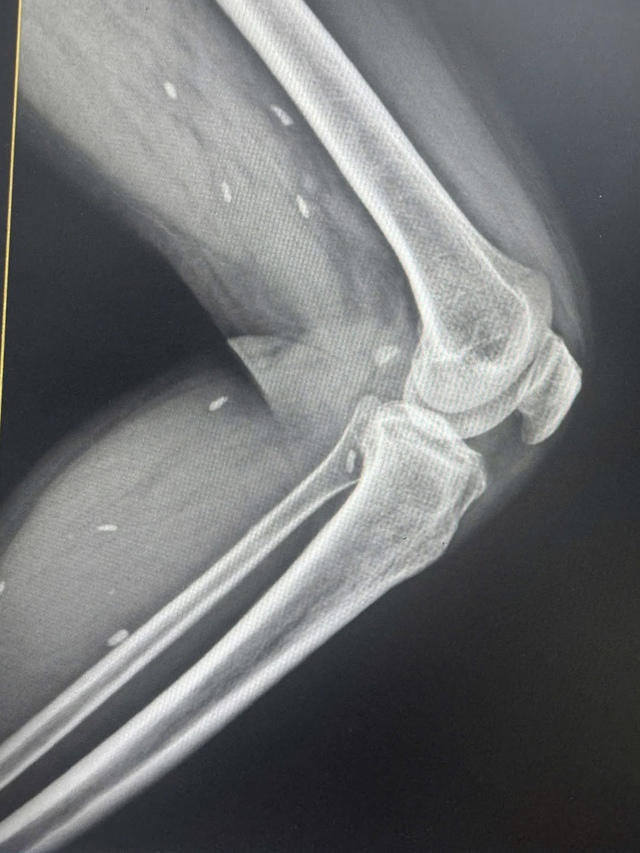

Nhiều kén sán kích thước như hạt gạo nằm rải rác ở các mô vùng xương đùi và cẳng chân bệnh nhân.

Bác sĩ Đỗ Hồng Thanh, Phó Giám đốc Trung tâm Y tế khu vực Thạch Hãn cho biết, kết quả X – quang phát hiện nhiều kén sán kích thước như hạt gạo nằm rải rác ở các mô vùng xương đùi và cẳng chân bệnh nhân.